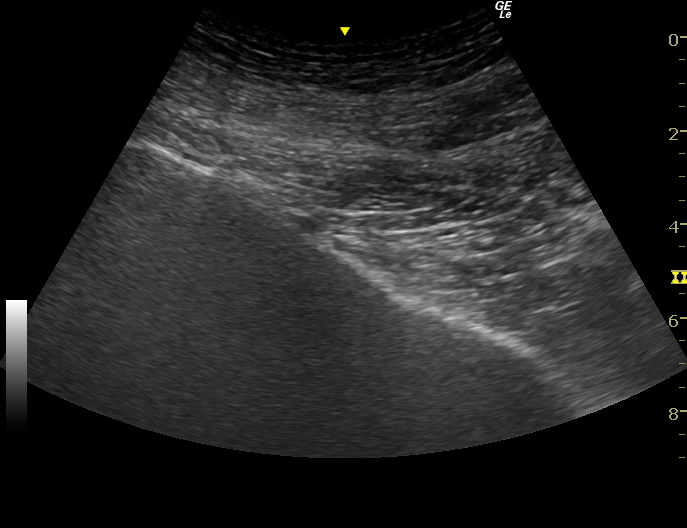

星状神経節ブロック

星状神経節は首の左右に一つずつある交感神経です。

この神経をブロックするとブロックした側の顔面や上半身の血液の流れが非常に良くなり、顔面や頭や上半身の痛みを効果的に軽減します。

当院ではより安全ブロックができるようにエコーを使用してブロック注射を行っています。